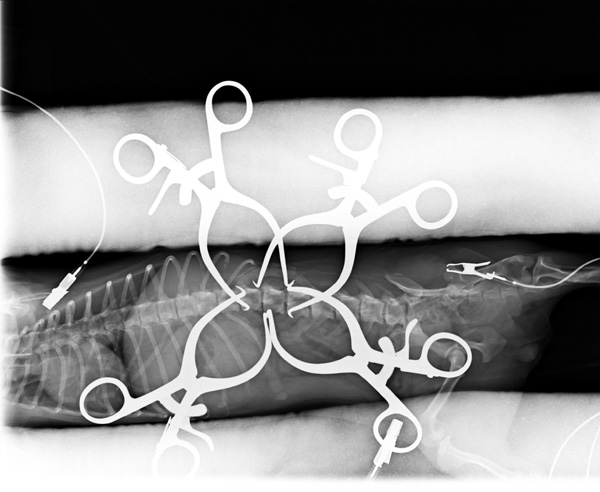

5~6歳以上の去勢手術をしていないオス犬に多い病気ですが、メス犬や去勢した犬に起こることもあります。お尻の筋肉が萎縮した結果、筋肉の隙間から直腸や膀胱が皮膚の下にとびでてしまいます。これにより便が出にくくなったり膀胱炎になったりします。手術をすることで機能回復および今後の致死的な状況を回避することができます。当院では去勢手術→結腸固定→前立腺固定→骨盤隔膜構成筋の縫縮→内閉鎖筋フラップ→浅臀筋フラップの順で通常腹側・臀部左右両側同時に行います。また老化以外に、筋肉が萎縮する原因があったり、腹圧がかかる原因があったりする場合も多いので、再発防止のためそれらの診断・治療も重要です。今回のワンちゃんも無事手術も終わり元気に退院しました。よかったね。